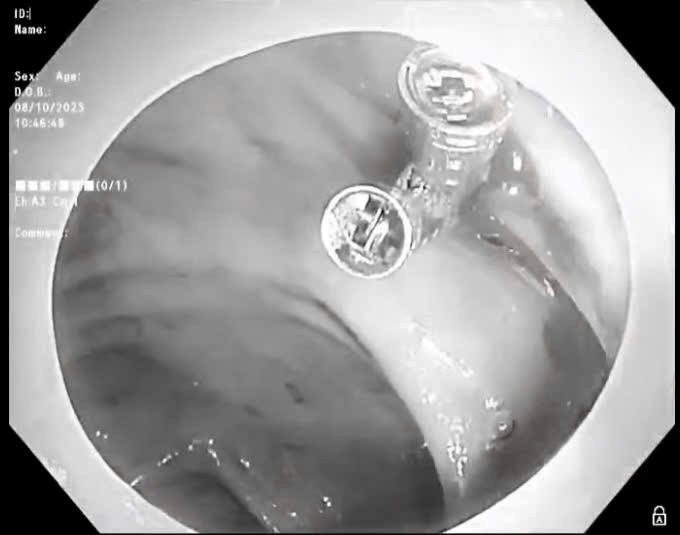

Quảng Trị: Kịp thời lấy viên thuốc nguyên vỏ bao kẽm kẹt ngang thực quản người bệnh

Wednesday 2026-01-07 02:38Ngày 6/1, Bệnh viện Hữu Nghị Quảng Bình, tỉnh Quảng Trị cho biết, vừa xử trí thành công 1 trường hợp bị dị vật thực quản đặc biệt, là viên thuốc còn nguyên trong bao kẽm. Dị vật gây đau...